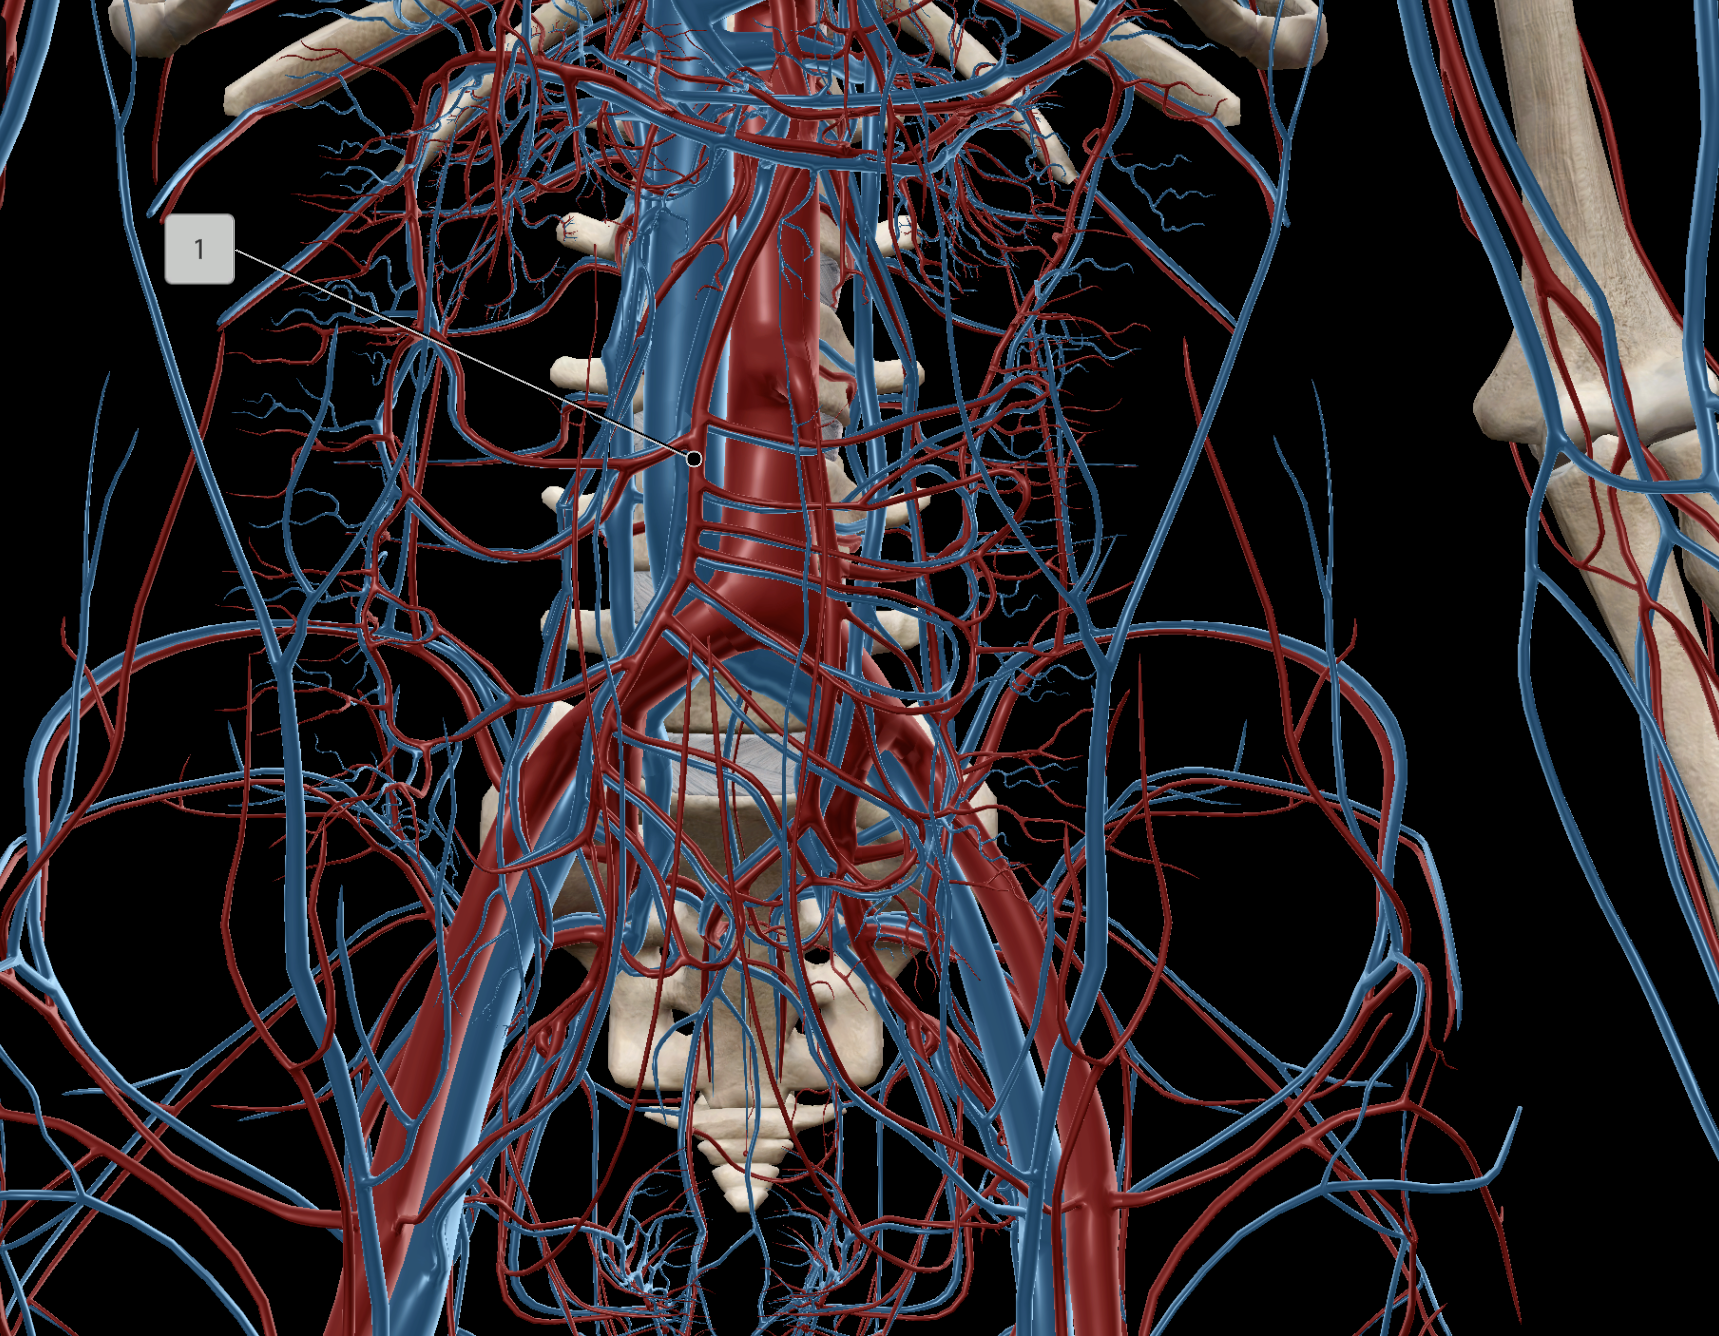

Abdominal Aorta

Superior Mesenteric Artery

Inferior Mesenteric Artery

Celiac Trunk